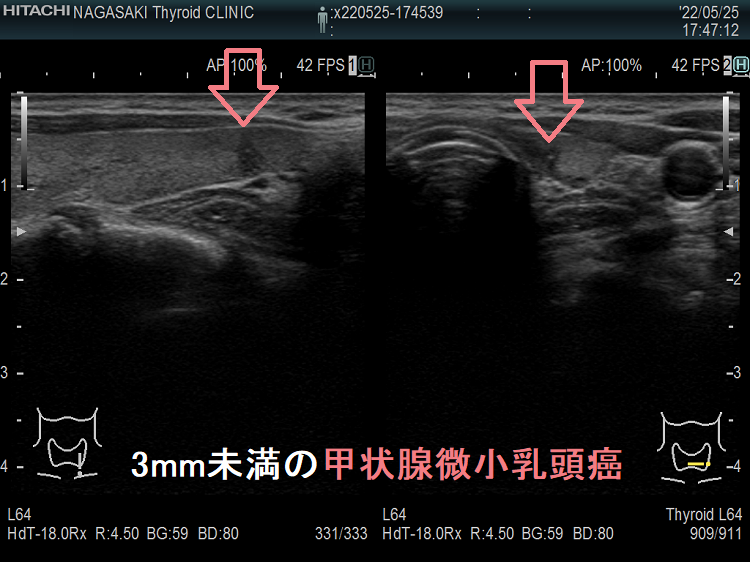

ケース④ 3mm未満の甲状腺結節

3mmの甲状腺結節 超音波(エコー)画像

3mm未満の甲状腺結節 超音波(エコー)画像;通常倍率では、甲状腺のう胞(甲状腺嚢胞)結節か判別できません。しかし、以下のように拡大すると↓

3mmの甲状腺結節(拡大、ドプラーモード)

3mmの甲状腺結節 超音波(エコー)画像 (拡大) ドプラーモード[eFlow(イー フロー)];拡大すれば内部血流が存在するため結節です。

ケース⑤ 3mm未満の甲状腺微小乳頭癌

3mm未満の微小乳頭癌 超音波(エコー)画像

3mm未満の甲状腺微小乳頭癌 超音波(エコー)画像:通常倍率では、破壊性の変化か甲状腺腫瘍か判別できません。しかし、以下のように拡大すると

3mm未満の甲状腺微小乳頭癌(拡大) 超音波(エコー)画像

3mm未満の甲状腺微小乳頭癌 (拡大) 超音波(エコー)画像:拡大すれば微細石灰化を伴う辺縁不整・粗雑な甲状腺微小乳頭癌であるのがはっきりします。